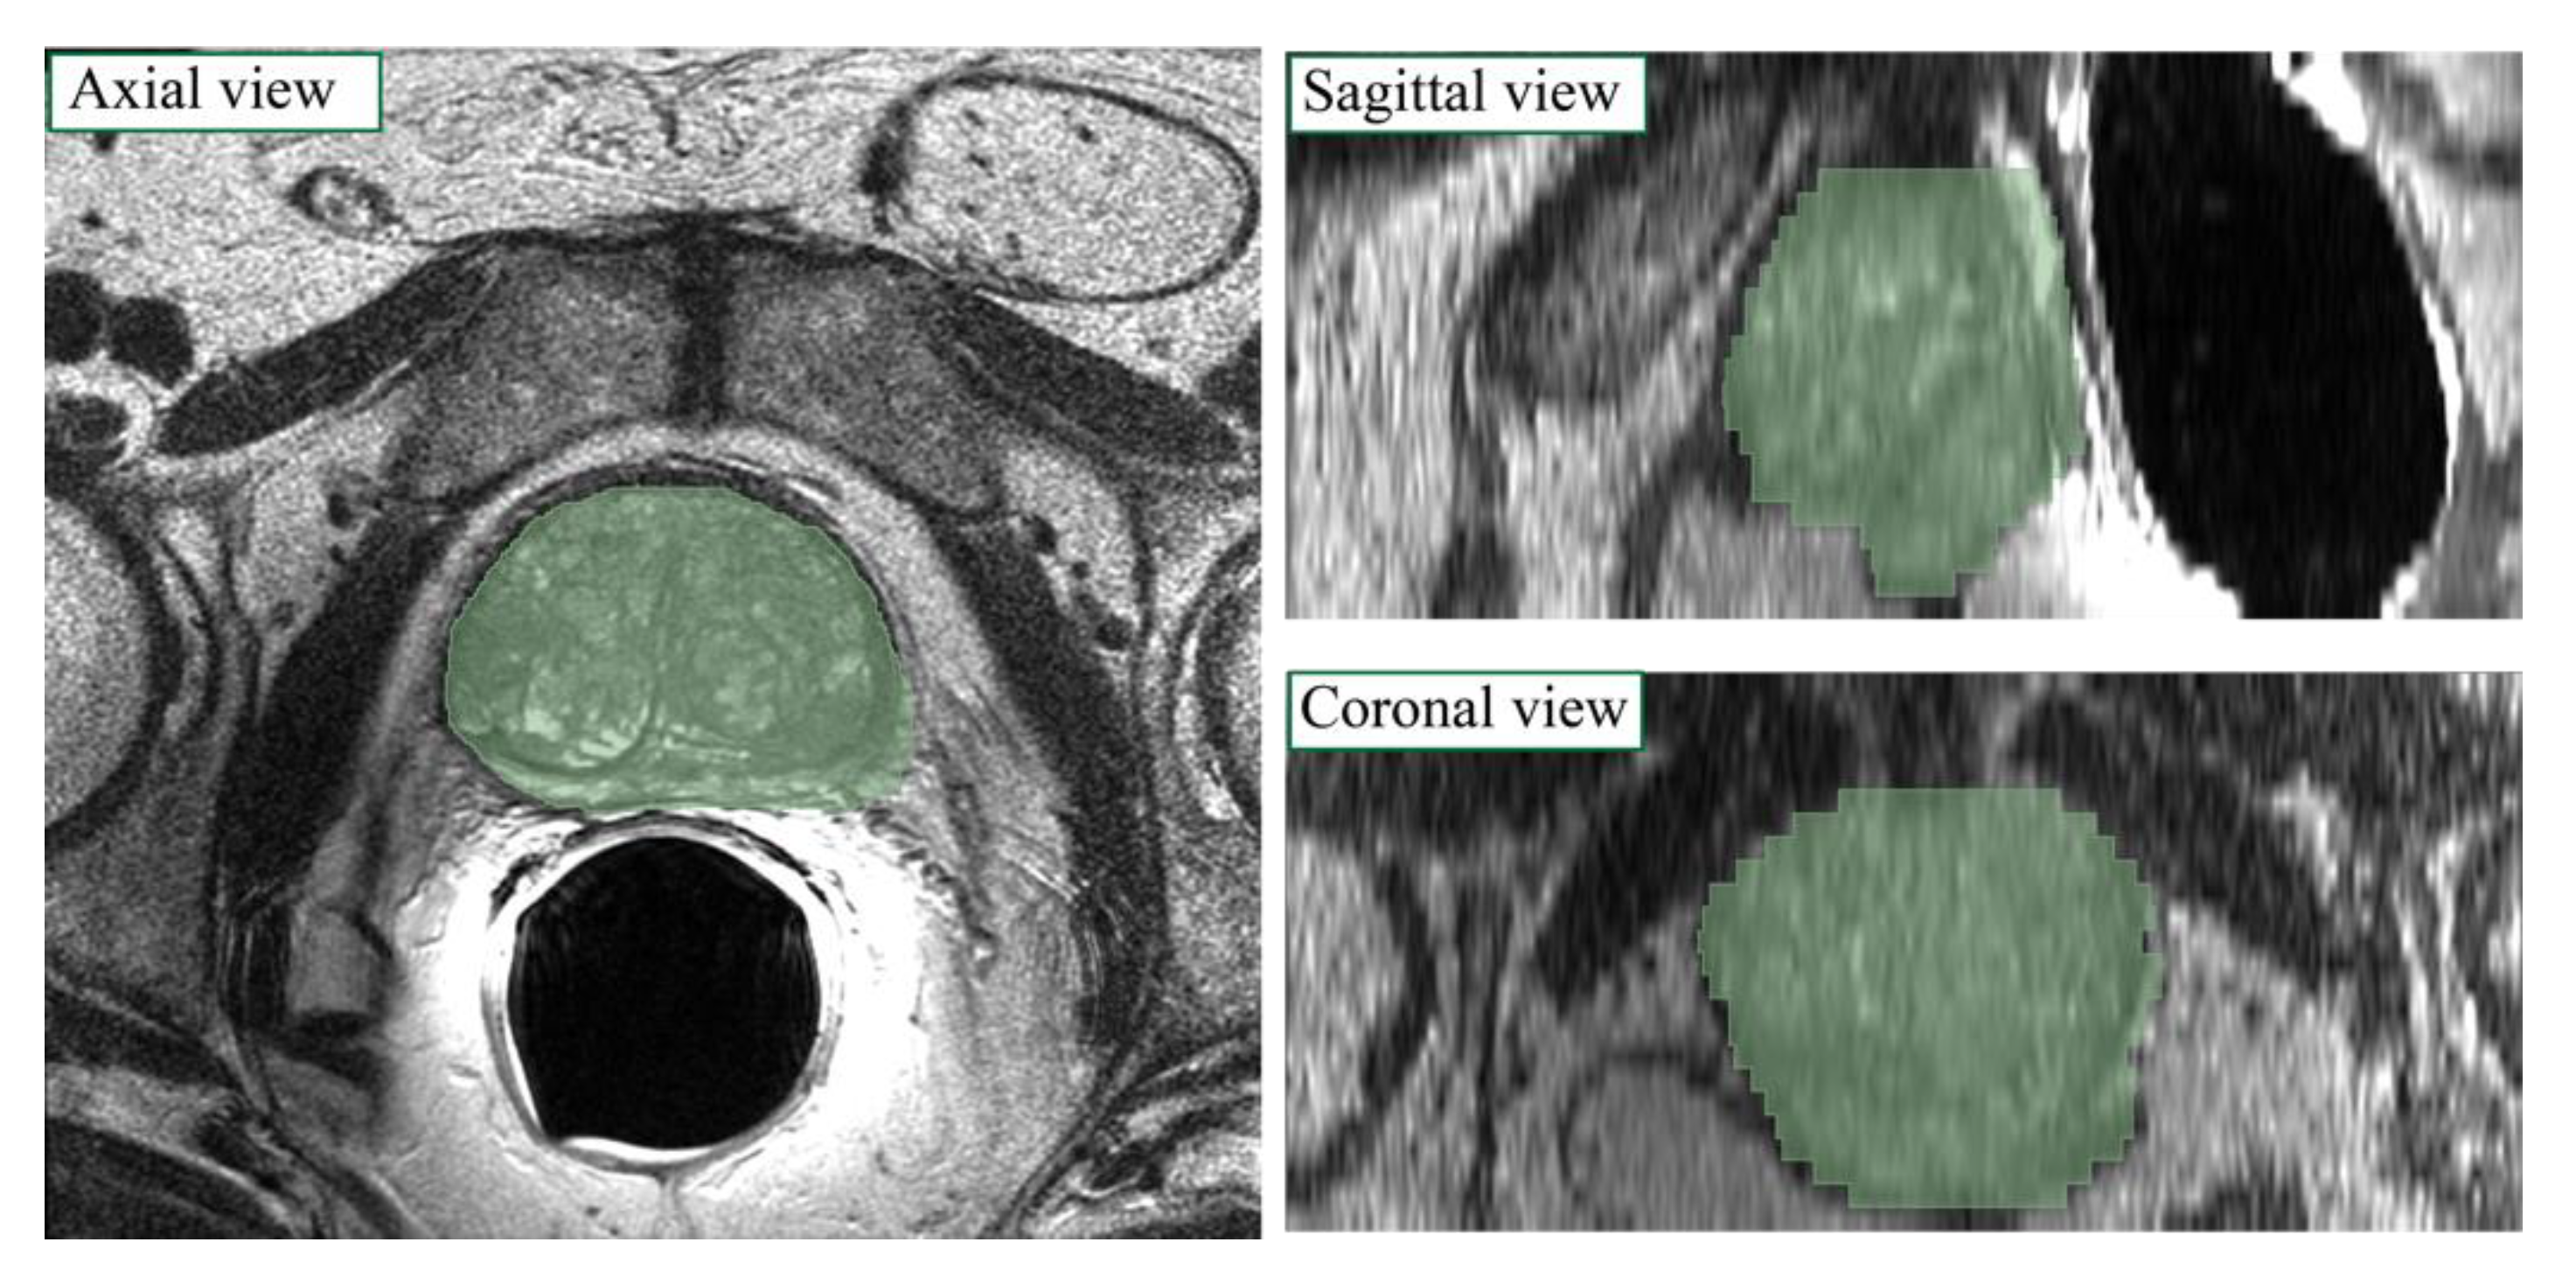

- Triangulation: the Alpha Shape Triangulation method is employed to divide the 3D surface into a variable number of triangles, with α = 30.

- 2D slices definition: to obtain the final 2D slices of the segmentation, the volume is divided into a number of planes whose z-coordinate corresponds to the number of slices. Then, similarly as to what was described previously, new vertices of the segmentation are found by computing the intersection between each ray and each triangle and taking the furthest point from the center, which is a first approximation of the points on the outermost surface.

- Final 3D volume reconstruction: the final 3D volume is obtained by stacking the 2D slices together, employing a hole-filling operation, and then a 3D morphological closing (spherical structural element, radius = 4). The post-processed binary volume is finally downsampled to the original resolution.